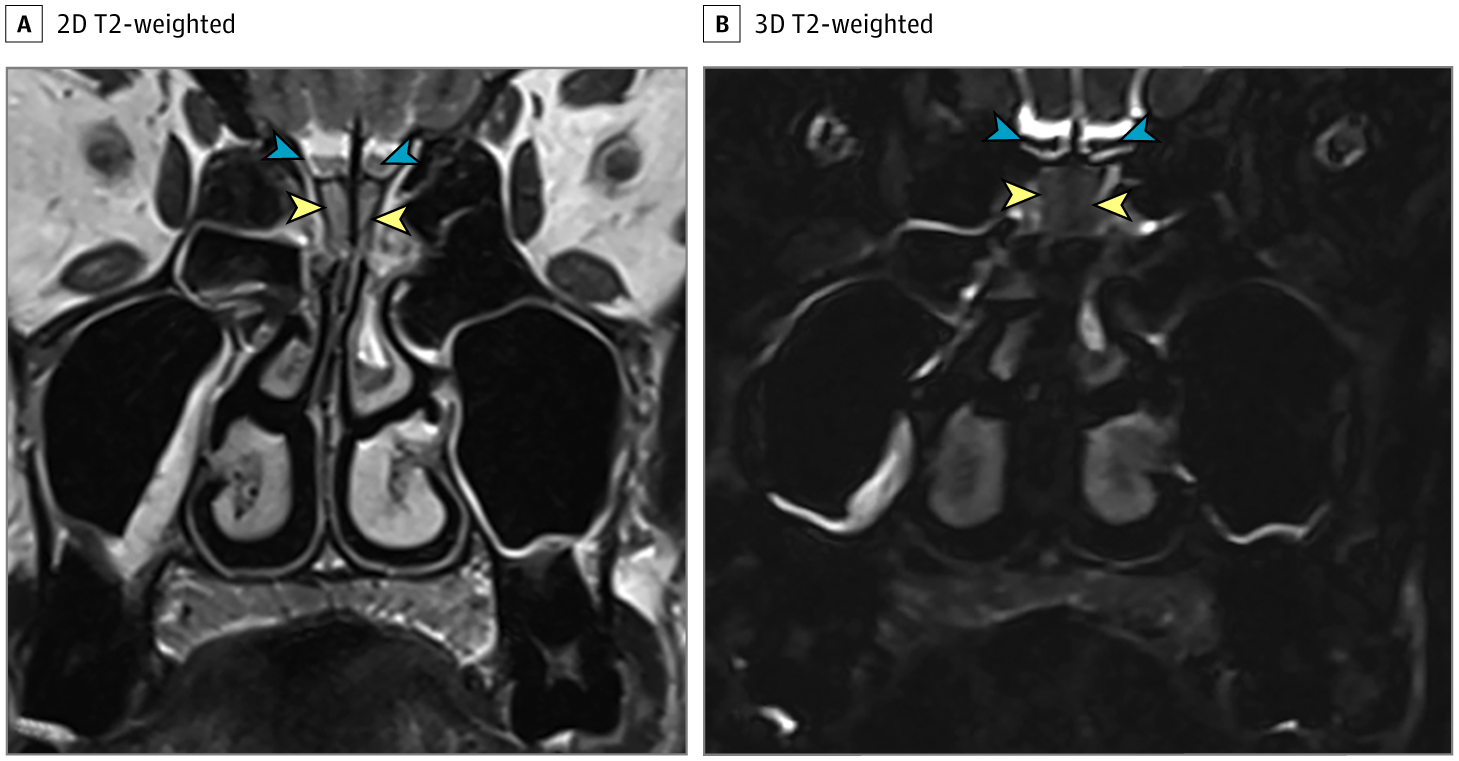

图1患者接受了鼻腔ct检查(图1),显示双侧嗅裂区的炎性阻塞,经鼻腔mri

图1:t2冠状位显示嗅球体积测量维生素d最早发现是其作用于钙稳态和